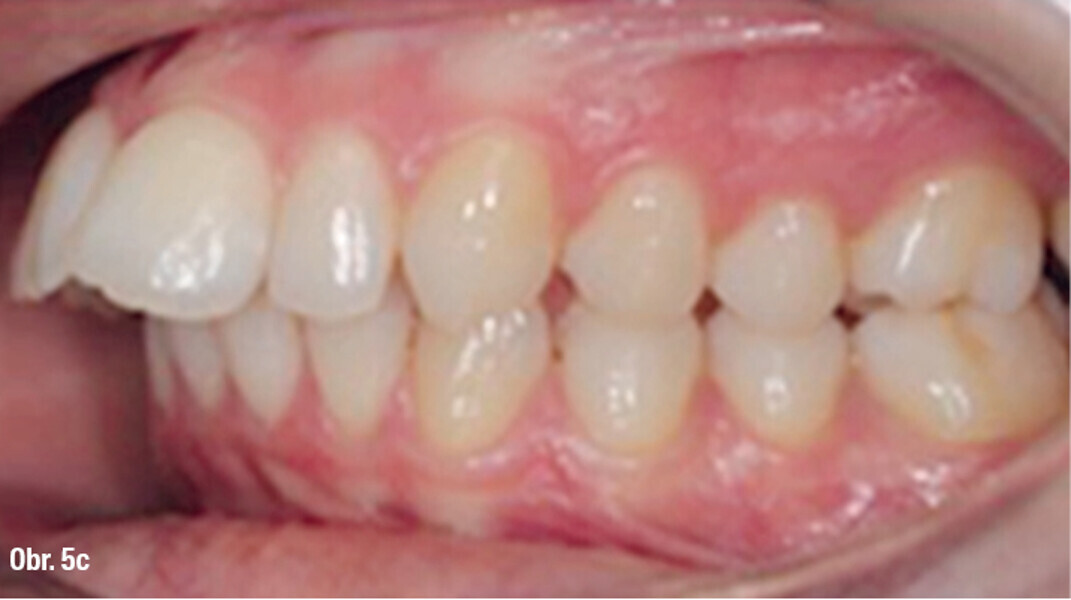

Distalizace horních molárů pomocí alignerů a cyklických sil